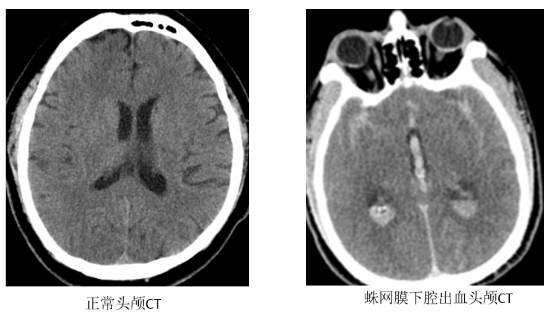

蛛网膜下腔出血是什么?

我们的大脑表面覆盖着三层保护膜,像三明治一样。中间那层薄薄的、像蜘蛛网一样的膜叫“蛛网膜”。

它和紧贴大脑的那层膜之间的空隙,就是“蛛网膜下腔”,里面流淌着营养大脑的脑脊液。

当这个腔隙里突然进了血,就是蛛网膜下腔出血。血液像化学刺激物一样,会引发大脑血管剧烈痉挛和全身强烈反应。

CT检查:首选,能快速判断大脑周围有没有出血。

腰椎穿刺:如果CT结果不明确,但症状高度怀疑,医生会进行腰穿。若脑脊液为均匀血性,即可确诊。